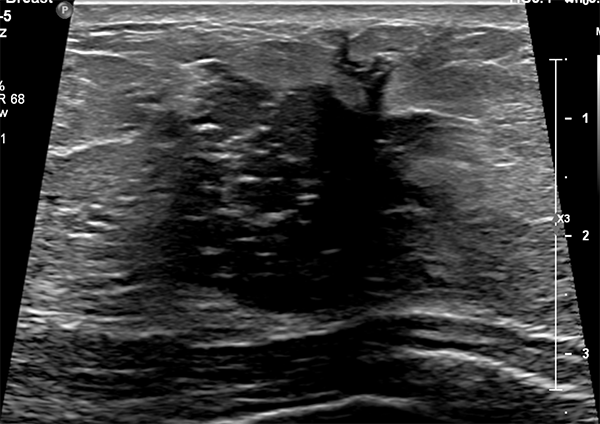

Breast imaging during pregnancy and lactation is already challenging due to both physiologic and structural changes to the breast. In addition, the American College of Radiology (ACR) reports that “Pregnancy-associated breast cancer (PABC) is increasing as more women delay child bearing into the fourth decade of life, and imaging of clinical symptoms should not be delayed.” At this time, guidelines from the American College of Radiology (ACR) recommend ultrasound as the first-line imaging modality for the evaluation of palpable masses in pregnant and lactating women, but data regarding breastfeeding women age 30 years and older are near nonexistent.

With this in mind, a team of breast imaging radiologists from the UC San Francisco Department of Radiology and Biomedical Imaging and the Mayo Clinic Department of Radiology set out to evaluate the diagnostic performance of targeted ultrasound as the primary imaging modality for the evaluation of palpable masses in lactating women, including those of advanced maternal age. Their second aim was to evaluate the added benefit of mammography.

Co-authors analyzed data from 167 symptomatic, breastfeeding women—at an average age of 35—who underwent targeted ultrasound. They found that ultrasound scored high marks, sensitivity and specificity of 100 percent and 70 percent respectively. Positive predictive value of an abnormal examination and positive predictive value of biopsy were 9.4 percent and 10 percent, respectively. In those who underwent mammography in addition to US, mammography added seven false-positive findings without additional cancer diagnoses. Specificity was lowered with the addition of mammography from 67 percent to 61 percent. These results support US as the primary modality for the evaluation of palpable lumps in breastfeeding women. You can read the full methodology of this study, which is the largest to date, in Radiology.